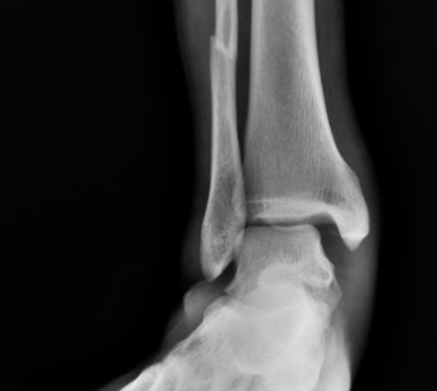

#踝关节骨折

如何预测Danis-Weber B型踝关节骨折下胫腓联合损伤?

Lauge-Hansen分型与Danis-Webe分型为最常见的踝关节骨折分型,在对下胫腓韧带损伤的指导意义上,旋后外旋II°骨折通常认为合并下胫腓前韧带的损伤,下胫腓联合趋于稳定,可能无需下胫腓联合螺钉固定。而Danis-Weber B型骨折定义为骨折位于下胫腓联合水平,可能合并下胫腓联合损伤。